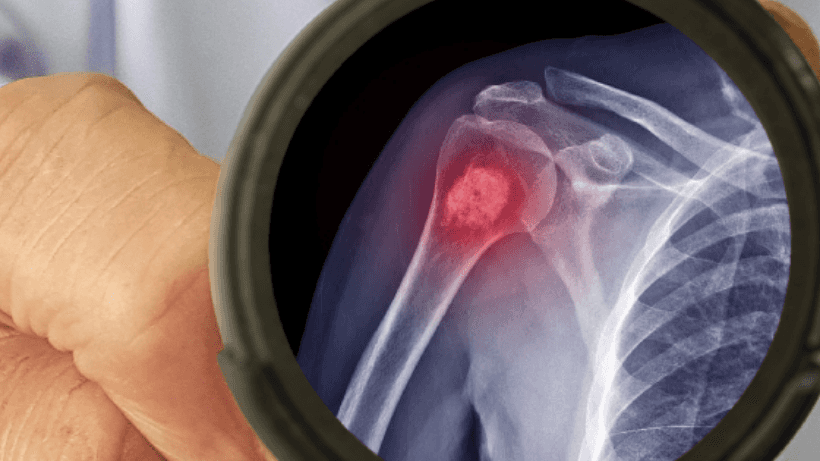

Qu’est-ce que le cancer des os et en quoi le cancer des os primaire est-il différent du cancer des os secondaire ?

Le cancer des os survient lorsque les cellules des os commencent à se développer de manière incontrôlée.. Il peut également se propager au-delà de l'os. Le cancer des os peut être primaire ou secondaire.

Comment diagnostique-t-on le cancer des os ?

Une fois que vous ressentez des symptômes etconsulter un médecin, votre médecin vous examinera pour identifier le problème et vous recommandera divers tests pour confirmer le diagnostic de cancer des os, comme des radiographies, des scintigraphies osseuses, des biopsies osseuses, Tomodensitogrammes, etc.